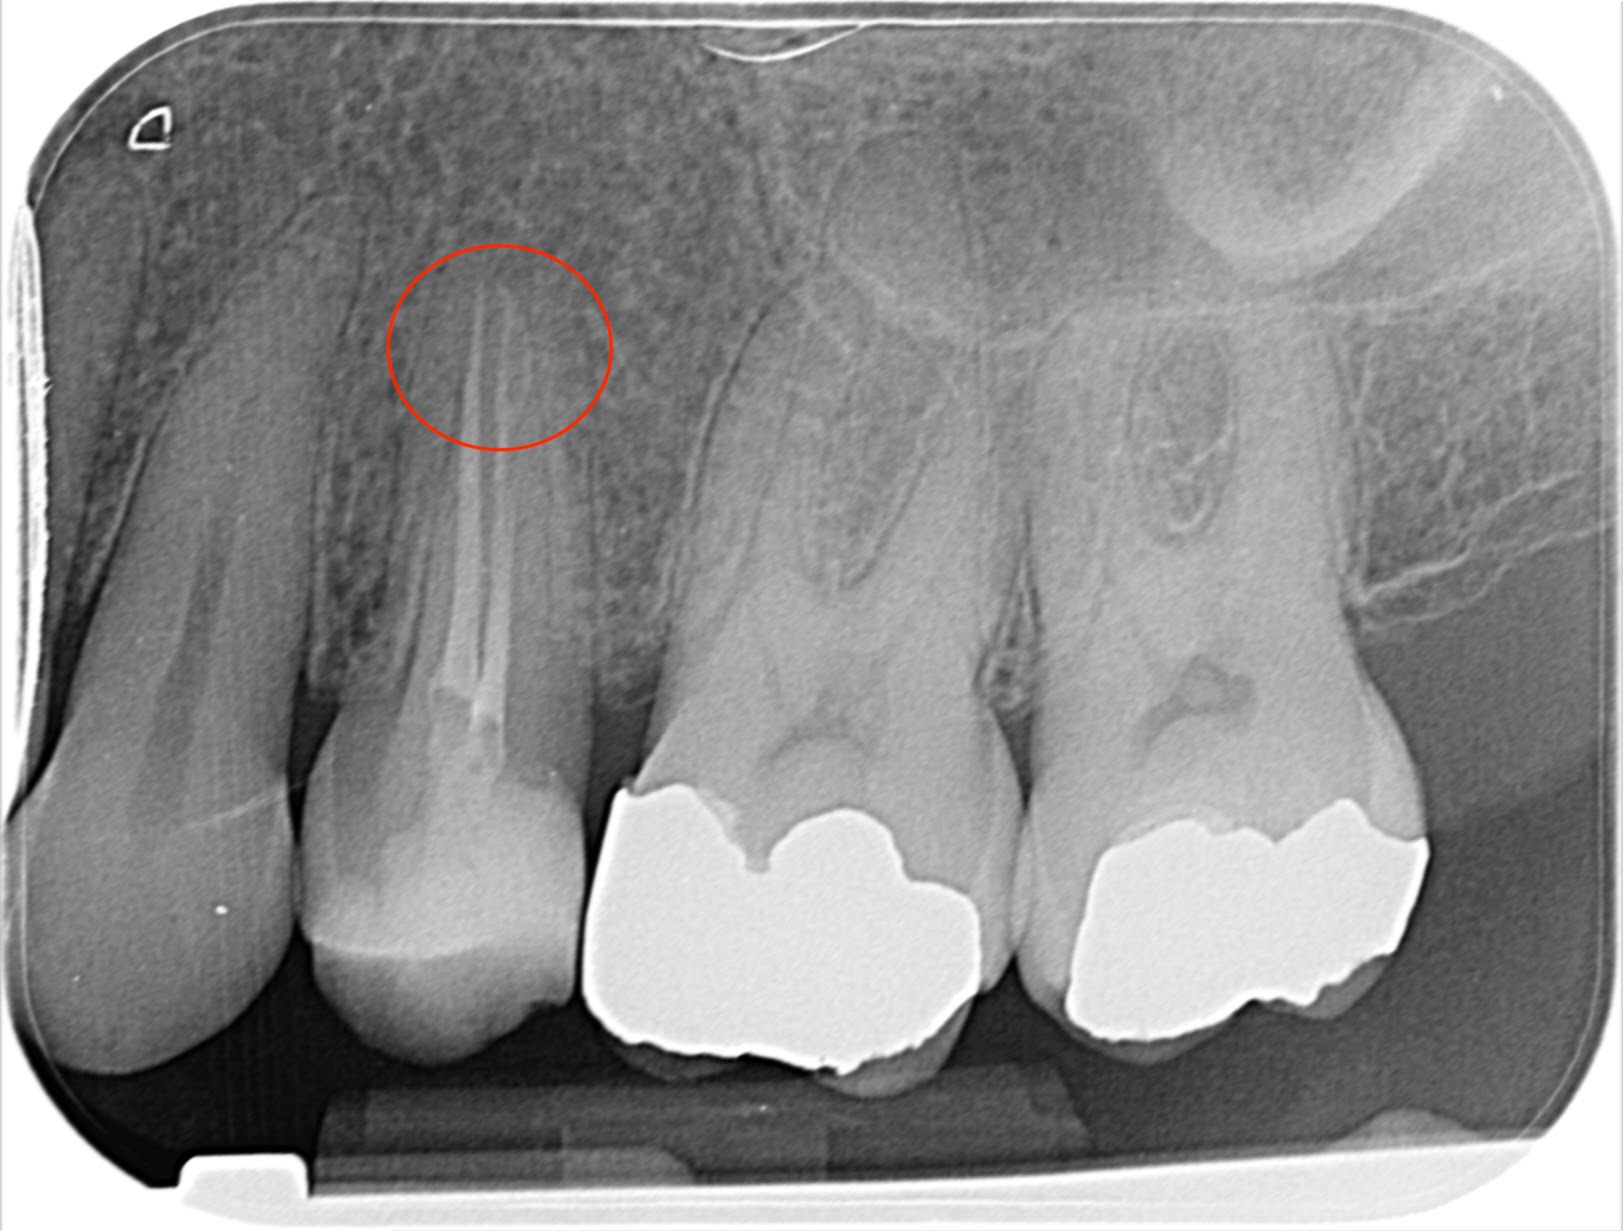

This upper second premolar Vertucci type 4 case was diagnosed with SIP and no clear apical change on IOPA.

It was prepared using 1403, 2004 and 2504 VS Flexi files from Toothsaver, as the canals appeared narrow and calcified on the pre-op IOPA. It was obturated with Onefill BC sealer and hydraulic condensation. On the post-op radiograph, you can see how the sealer-based obturation has filled the apical bifurcation of the buccal canal really nicely, which should help to achieve a positive outcome.